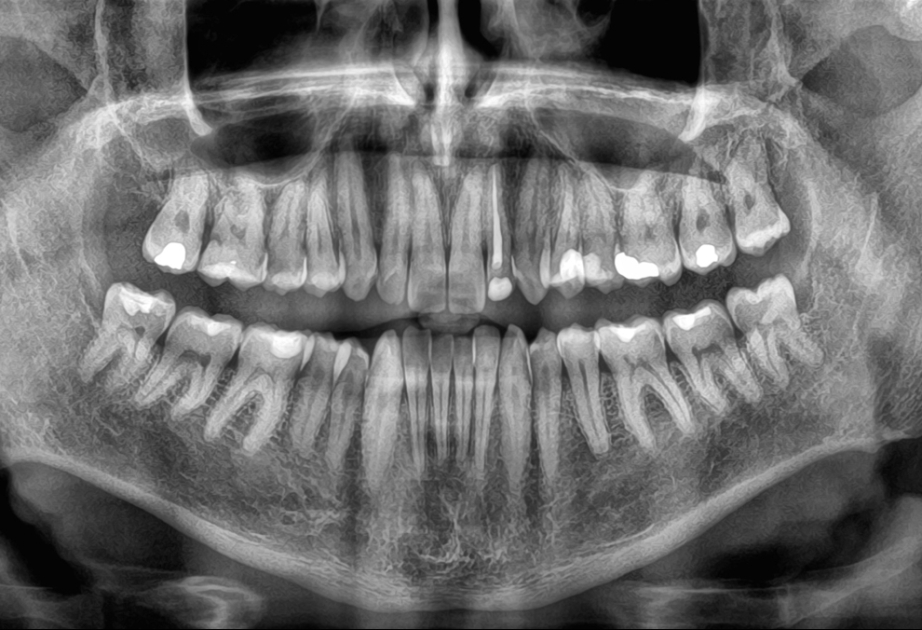

Yeni bir araşdırma göstərib ki, yaşlı insanlarda dişlərin sürətlə itirilməsi ölüm riskinin artması ilə əlaqəlidir. Çinli alimlər 3,5 il ərzində 8073 yaşlı insanı izləyərək belə nəticəyə gəliblər.

AZƏRTAC “sciencealert.com” portalına istinadla xəbər verir ki, tədqiqatın nəticələrinə görə, dişlərin itirilmə sürəti nə qədər yüksəkdirsə, bütün səbəblərdən ölüm riski də bir o qədər artır. Bu əlaqə yaş, cins, təhsil, içki və məşq vərdişləri kimi digər amillər nəzərə alındıqdan sonra da qalır. Mütəxəssislər bildirirlər ki, dişlərin itirilməsi birbaşa ölümə səbəb olmur, lakin diş itkisinə yol açan sağlamlıq problemləri, məsələn, iltihab, pis qidalanma və ürək xəstəlikləri ömrü qısalda bilər. Alimlər diş itkisinin insanın ümumi sağlamlıq vəziyyətini qiymətləndirmək üçün göstərici kimi istifadə oluna biləcəyini vurğulayırlar. Həkimlər dişlərin qorunması üçün müntəzəm diş həkimi müayinəsini, gündə iki dəfə fırçalamağı və siqaretdən uzaq durmağı tövsiyə edirlər.